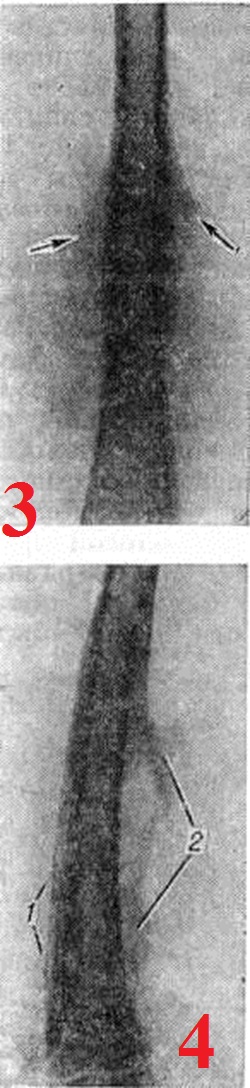

Рис. 3.

Прямая рентгенограмма бедра больного с опухолью Юинга: линейные слоистые периостальные наслоения (указаны стрелками) диафиза бедренной кости.

Рис. 4.

Боковая рентгенограмма бедра ребёнка 11 лет, больного остеомиелитом: неровные, «бахромчатые», периостальные наслоения (1) на передней поверхности бедренной кости; беспорядочные «рваные» периостальные остеофиты (2) вследствие разрывов и отслоений надкостницы на задней её поверхности.

Рентгенодиагностика. Рентгенологические исследование выявляет локализацию, распространённость, форму, размеры, характер структуры, очертания периостальных наслоений, их взаимоотношения с корковым слоем кости и окружающими тканями. Рентгенологически различают линейные, бахромчатые, гребневидные, кружевные, слоистые, игольчатые и другого вида периостальные наслоения. Хронические, медленно текущие процессы в кости, особенно воспалительные, обычно вызывают более массивные напластования, как правило, сливающиеся с основной костью, что ведёт к утолщению кортикального слоя и увеличению объёма кости (рисунок 1). Быстро протекающие процессы ведут к отслоению надкостницы гноем, распространяющимся между ней и кортикальным слоем, воспалительным или опухолевым инфильтратом. Это можно наблюдать при остром остеомиелите, опухоли Юинга (смотри полный свод знаний Юинга опухоль), ретикулосаркоме (смотри полный свод знаний). Видимая в этих случаях на рентгенограмме линейная полоска новой кости, образованная надкостницей, оказывается отделённой от кортикального слоя полосой просветления (рисунок 2). При неравномерном развитии процесса таких полосок новой кости может быть несколько, в результате чего образуется картина так называемый слоистых («луковичных») периостальных напластований (рисунок 3). Гладкие, ровные периостальные наслоения сопровождают поперечную патологическую функциональный перестройку. При остром воспалительном процессе, когда под периостом скапливается гной под большим давлением, надкостница может разрываться, и на участках разрывов продолжает продуцироваться кость, давая на рентгенограмме картину неровной, «рваной» бахромы (рисунок 4).